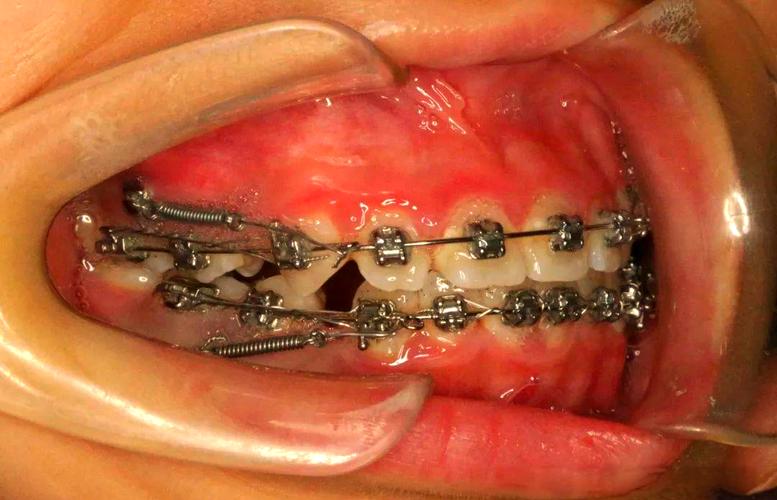

种植钉,又称微种植体支抗,是通过外科手术植入牙槽骨内的微型钛钉,直径通常为1.2-2.0mm,长度6-12mm,其作用原理是利用骨组织与种植钉表面的“骨结合”提供稳定的支抗力量,从而实现牙齿的精准移动,在二次正畸中,由于患者可能存在牙槽骨吸收、牙齿倾斜度大、支抗牙条件差等问题,传统支抗方式(如头帽、颌间牵引)往往难以满足需求,而种植钉的优势尤为突出:

二次正畸常涉及需要强支抗的病例,如压低伸长的磨牙、关闭拔牙间隙、纠正中线偏移等,部分患者首次正畸后因磨牙伸长导致咬合过深,种植钉可植入颧牙槽嵴或腭部,通过施加持续、稳定的压低力量,避免支抗牙(如前牙)发生不必要的移动,从而精准恢复咬合垂直距离。

二次正畸患者常伴有牙齿扭转、倾斜、埋伏等问题,种植钉可作为“移动的支点”,通过改变施力方向,实现牙齿的整体移动、控根移动或转矩控制,对于前牙散开复发且伴有唇倾的情况,种植钉可在腭部植入,通过牵引钩施加舌向力,同时配合唇侧牙套的托槽,既关闭间隙又改善牙根位置,避免“黑三角”加重。

首次正畸后,若患者未保持好或存在夜磨牙习惯,易导致后牙伸长,引起咬合紊乱、颞下颌关节问题,种植钉可精准压低伸长的磨牙,恢复咬合平面,对于上颌第一磨牙伸长,种植钉可植入腭中缝或颧牙槽嵴,通过镍钛辅弓或直接结扎施加压低力,避免压低过程中前牙伸长或支抗丧失。

二次正畸常需重新评估拔牙方案,如首次拔牙后间隙未完全关闭、或因复发出现间隙,种植钉可提供“绝对支抗”,避免非目标牙移动,在关闭上颌拔牙间隙时,种植钉植入上颌后牙区,通过滑动法或关闭曲法,将前牙整体向后移动,确保后牙支抗稳定,防止间隙关闭后后牙前移导致咬合关系紊乱。